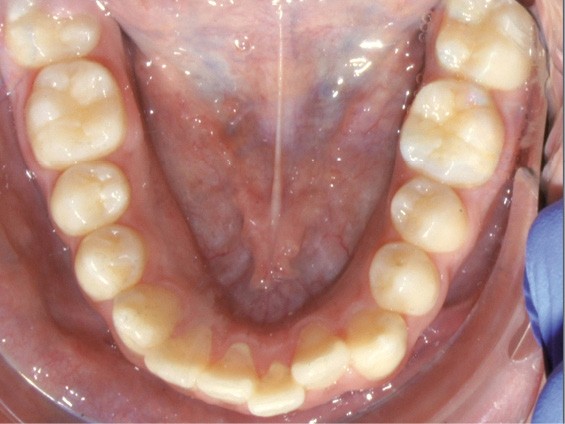

Examen endo-buccal (fig. 2a-e)

L’arcade mandibulaire est également parabolique avec un encombrement antérieur se traduisant par la vestibulo-position de 31 et la linguo-position de 32. L’encombrement est de 3 mm.